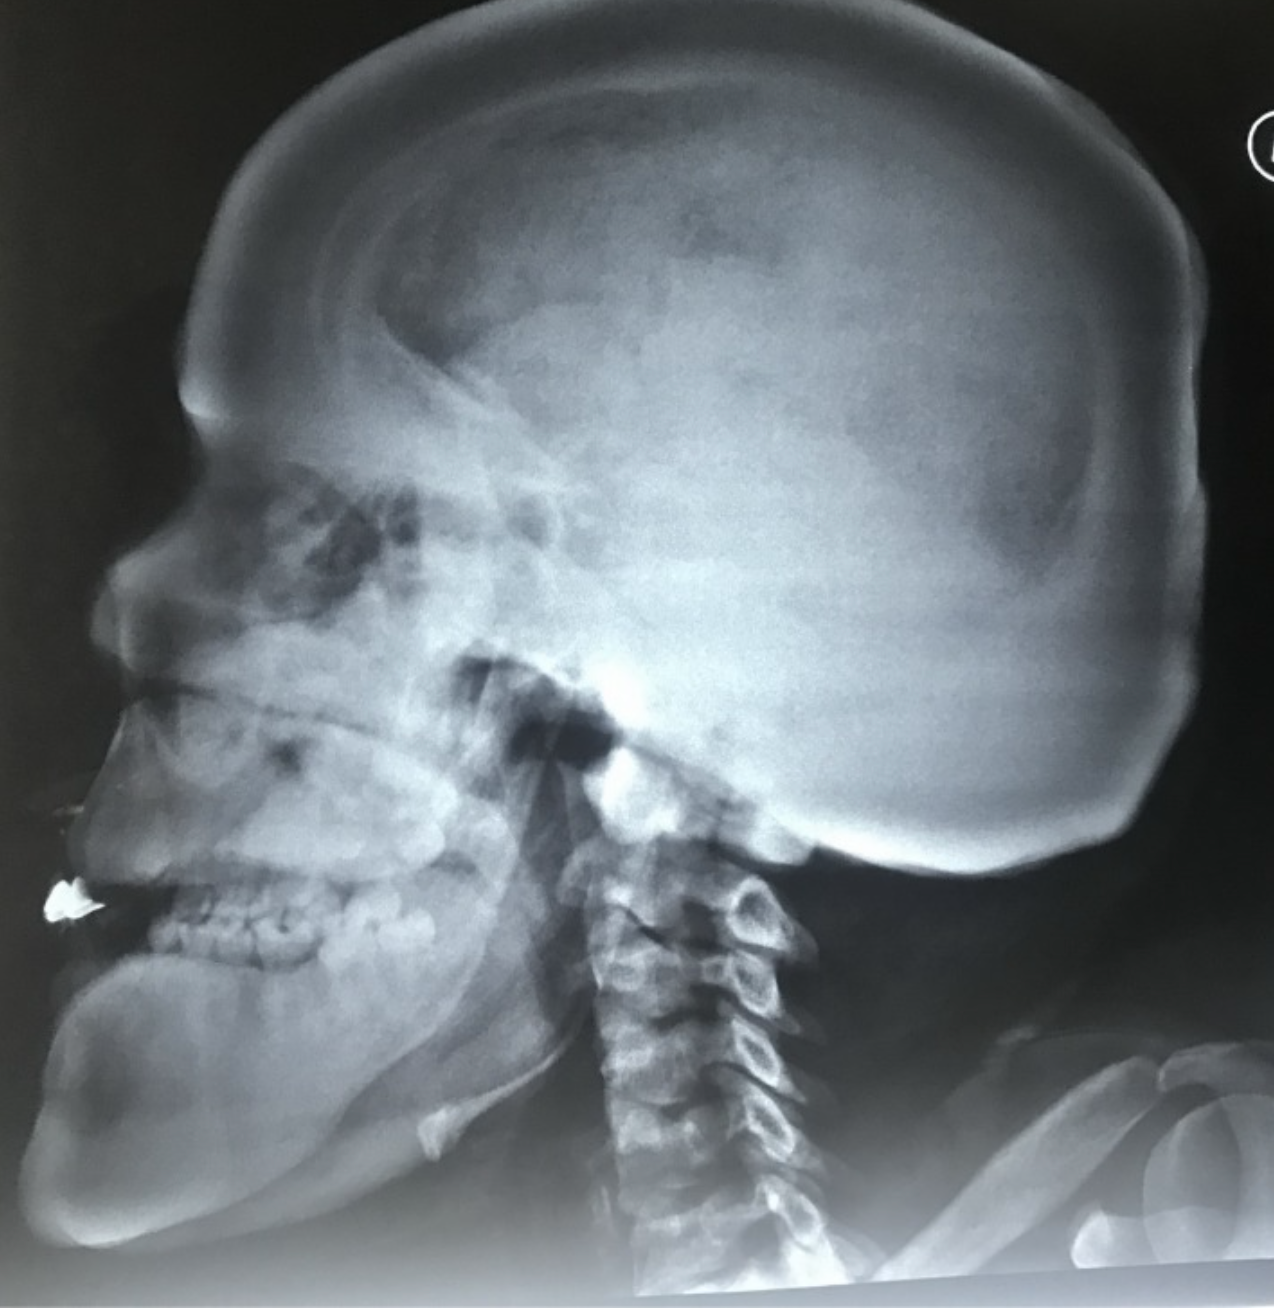

Treacher Collins syndrome

1 case question available

Case Discussion

In Treacher Collins syndrome, 1st and 2nd branchial arch structures are affected but the inner ear structures are normal.

Treacher colins Syndrome